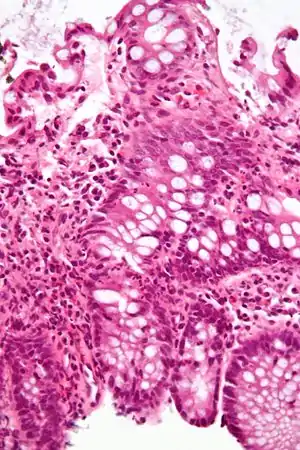

| Micrograph showing inflammation of the large bowel in a case of inflammatory bowel disease. Colonic biopsy. H&E stain. | |